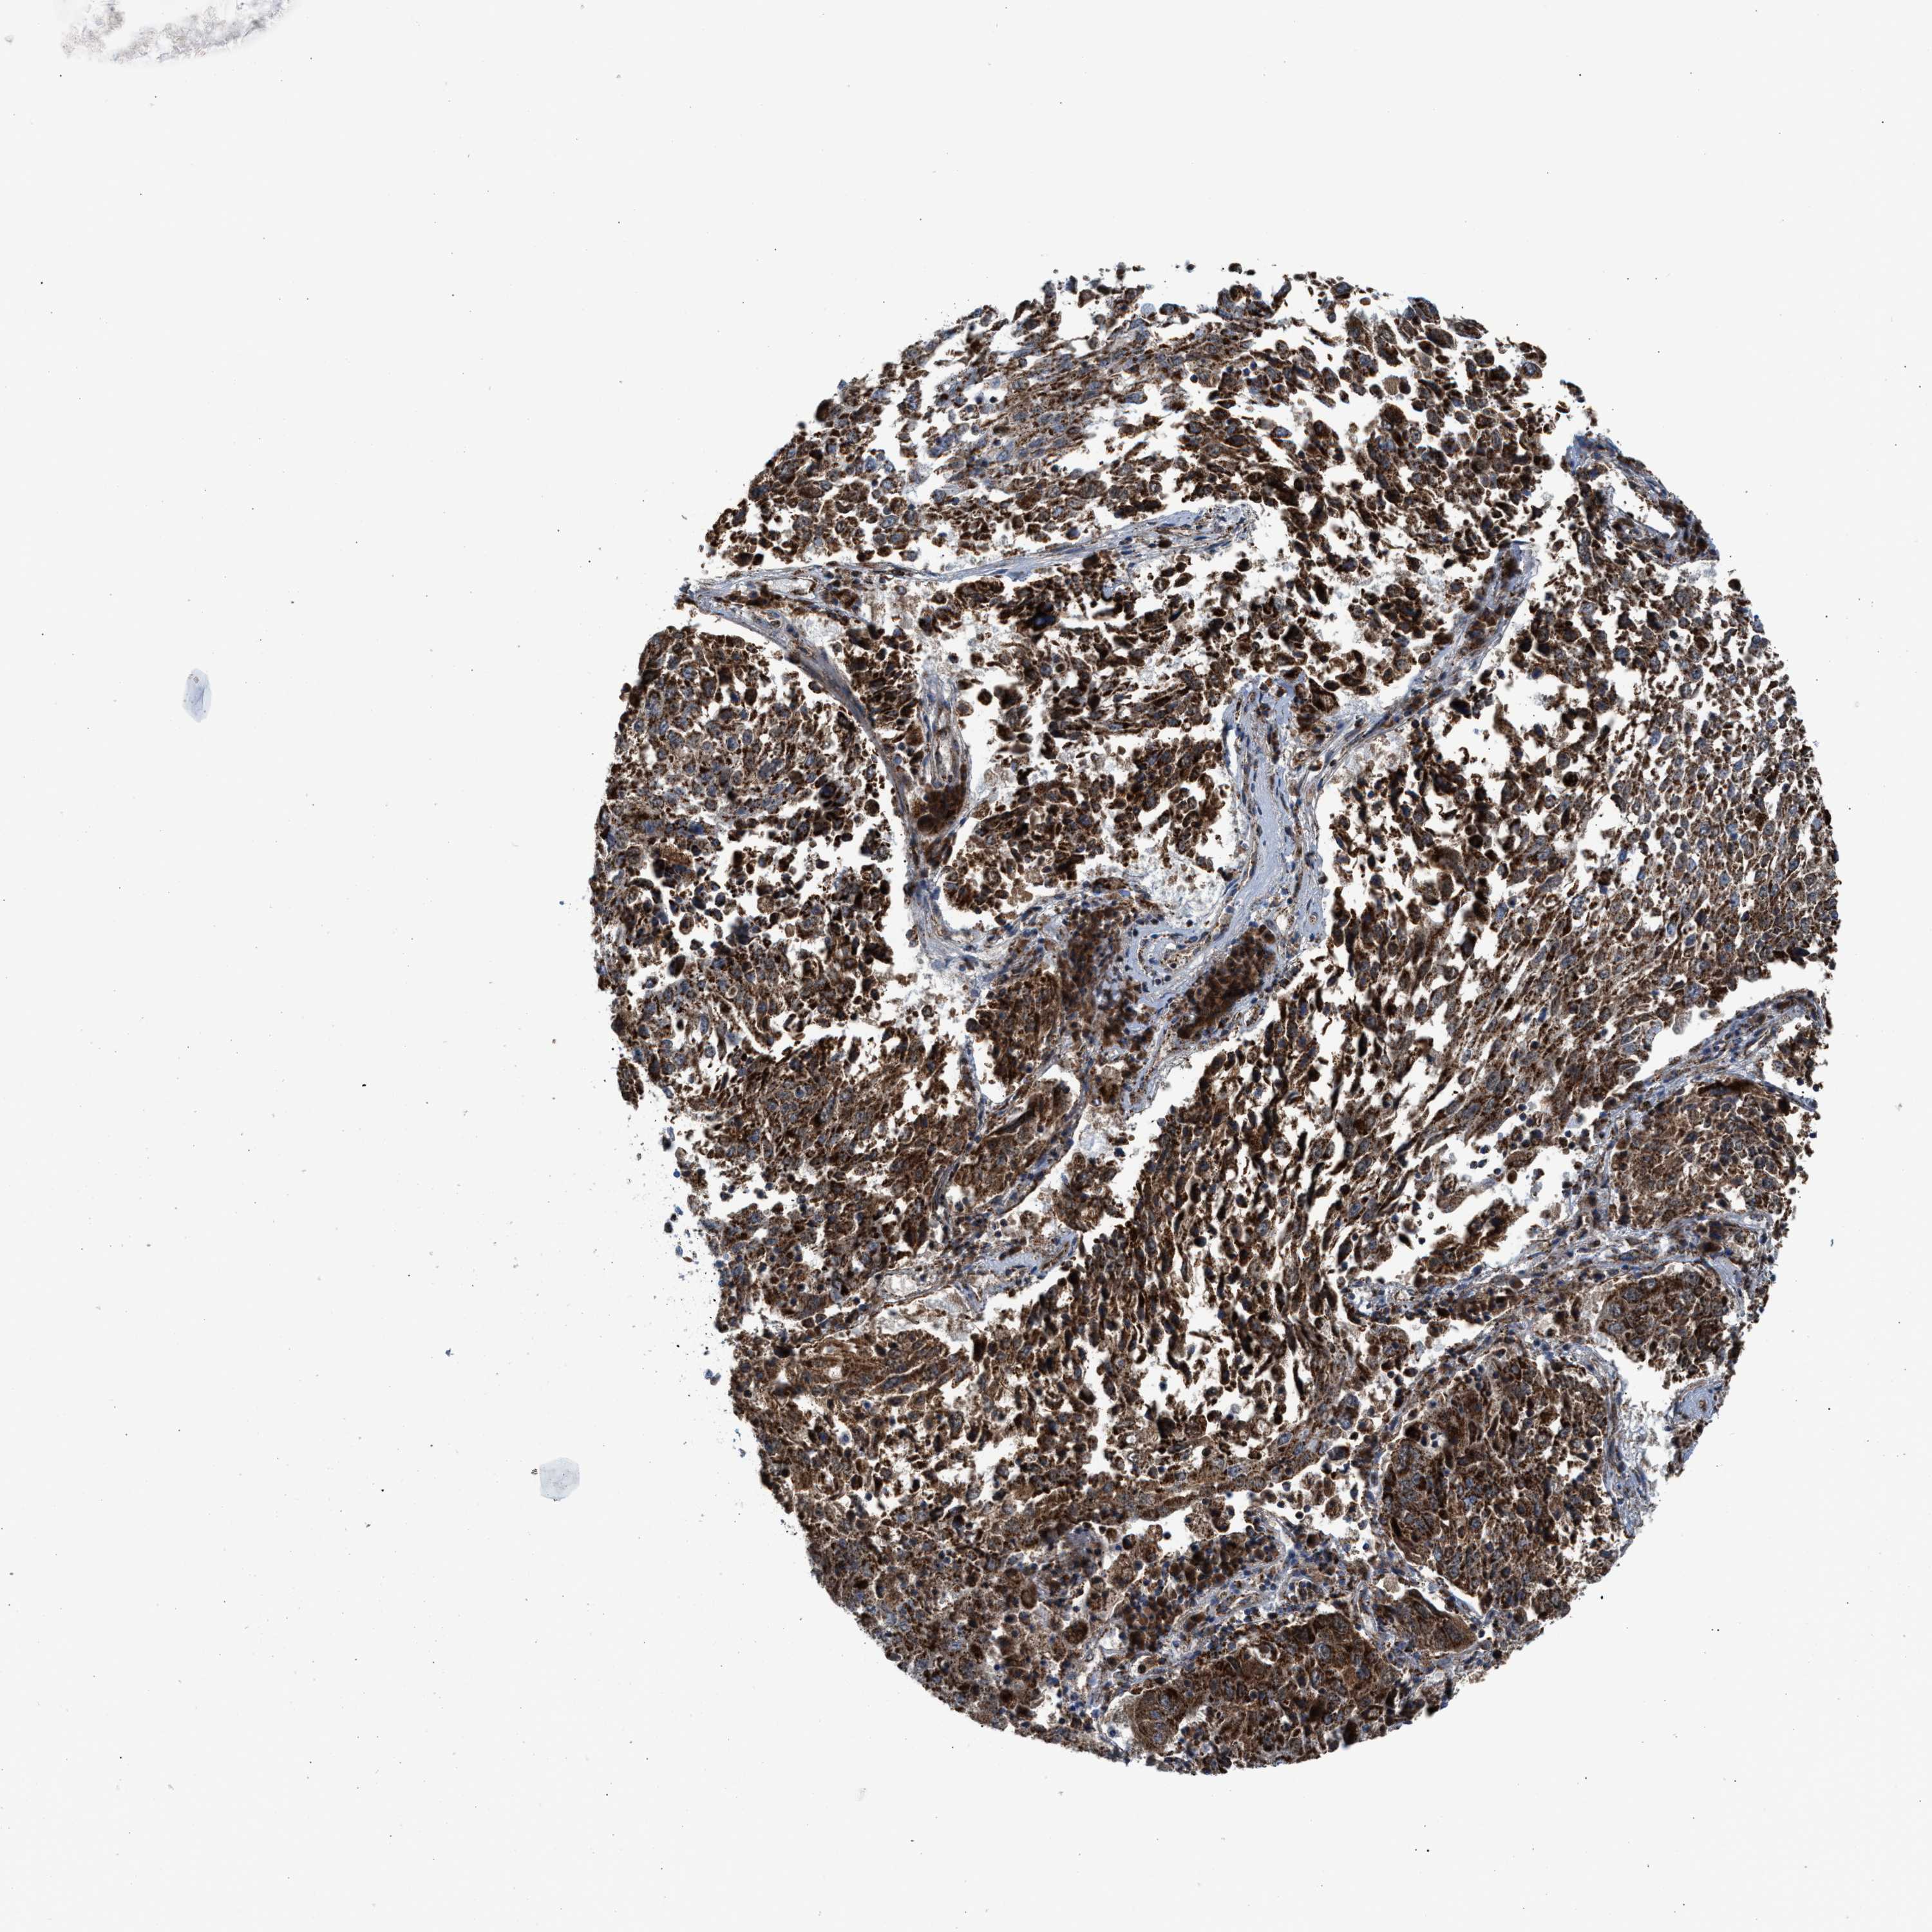

CANCER LUNG CANCER Show tissue menu

LUAD TCGA LUAD VALIDATION LUSC TCGA LUSC VALIDATION PROTEIN LUAD CPTAC PROTEIN LUSC CPTAC PROTEIN EXPRESSION

PMPCA is not prognostic in Lung Adenocarcinoma (TCGA)

: 33.46

Average pTPM 34.2

Number of samples 497